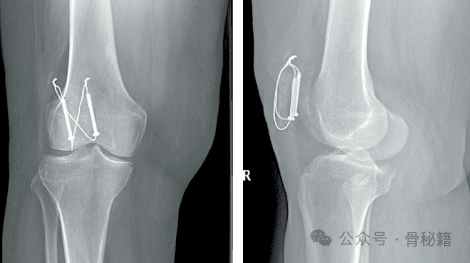

以垂直、平行的方式放置 1.6 mm 克氏针或 4.0 mm 松质骨螺钉,以维持复位并锚定环扎线。还可以将复位装置取下,以使克氏针以逆行方式穿过骨折部位。然后将 14 或 16 号血管导管或等效物穿过邻近髌骨、克氏针尖端后方的髌骨和股四头肌腱。这可以最大限度地减少环扎线和骨头之间的软组织。然后将 18 号线以圆形或十字形 8 字形穿过导管。确保关节面复位后,将线拉紧。当使用八字形图案时,内侧和外侧环应对称收紧。然后将克氏针的近端弯曲、扭转,使其面向后,围绕环扎线,然后埋入近端髌骨中。然后切割克氏针多余的远端

克氏针张力带法

空心钉张力带法